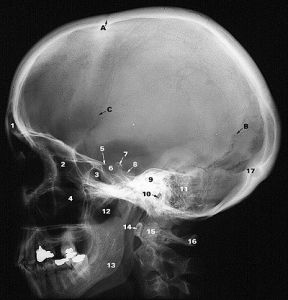

頭顱X線平片其它輔助檢查:

與身體其他部為的骨巨細胞瘤相同 呈單純溶骨性改變,最常見的部位是蝶骨近中線處 軟組織樣腫瘤擴張常見,軟組織影與骨質破壞有關,但影像學上沒有特異性特徵來明確診斷。

頭顱X線平片可分為三種類型:

1.多囊型 不規則多房性骨破壞區,內有殘存粗大骨梁,邊緣銳利規則,呈高密度線條狀影。

2.單囊型 呈膨脹性骨破壞區,瘤內無骨小梁間隔X線檢查如骨囊腫,內外板分離,周圍有高密度骨硬化帶

3.單純骨破壞型 非膨脹性骨破壞無囊腫樣表現

CT表現為均一高密度病灶,不強化或輕微強化。MRI可明確腫瘤的部位及與周圍組織的解剖關係。